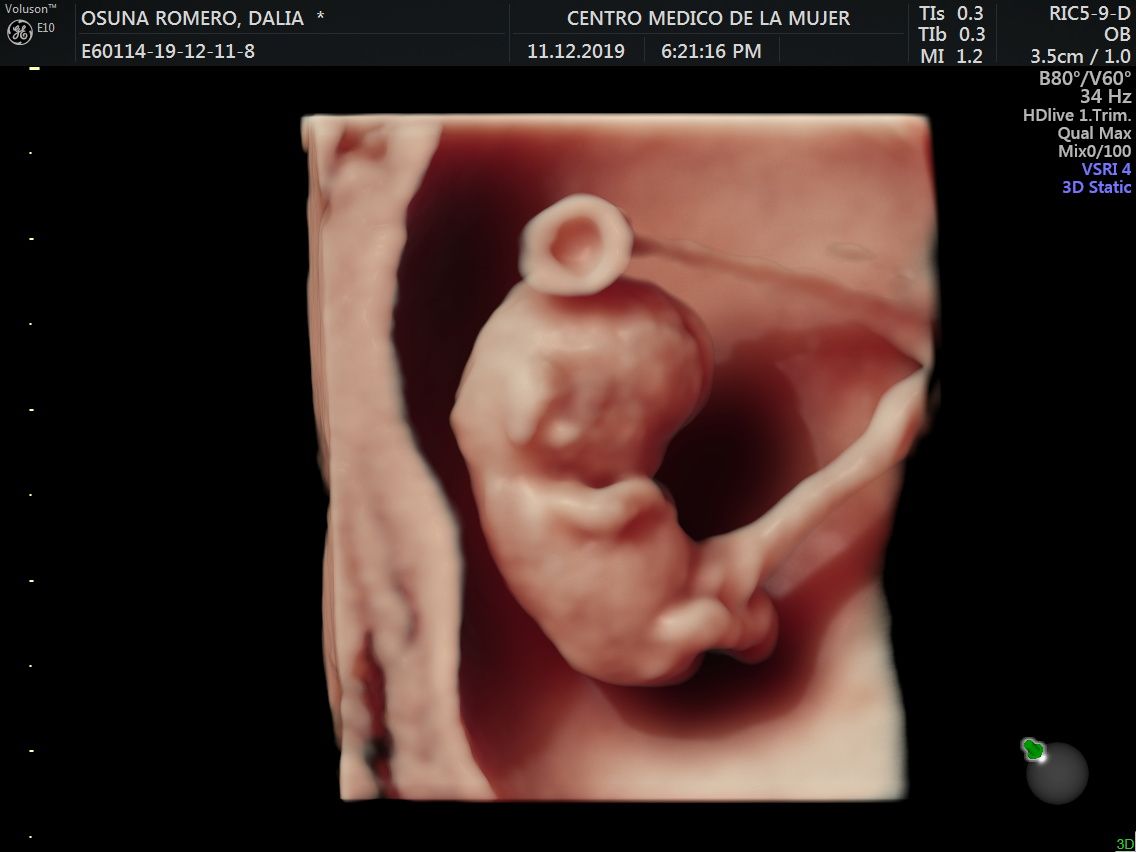

Fotos y videos

ECO Anatómico

Consiste en la evaluación especifica de cada organo y sistema del bebé con medidas detalladas de cada parte para evaluar su crecimiento proporcional.